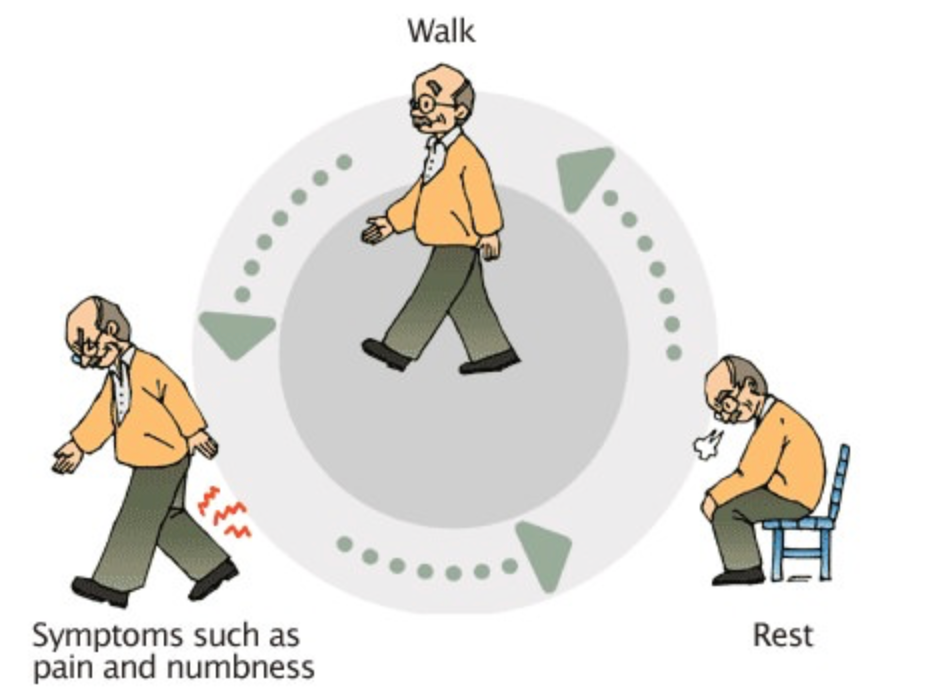

Unlike simple back pain, lumbar canal stenosis often causes leg symptoms that worsen with standing or walking and improve with sitting or bending forward. Early diagnosis and appropriate management are important to maintain mobility and quality of life.

Symptoms vary depending on the severity and number of levels involved.

- Low back pain or stiffness

- Leg pain, heaviness, or numbness while walking

- Tingling or weakness in the legs

- Neurogenic claudication (leg pain after walking a certain distance)

- Relief of symptoms on sitting or bending forward